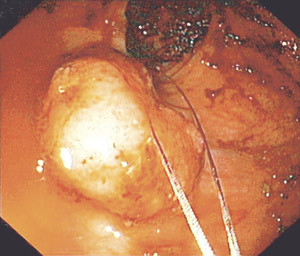

In the rectosigmoidoscopy, following evacuation with 240 ml Klyx, we advanced 30 cm inside the anal canal before having to stop owing to poor cleansing more proximally. Distal to this level emptying was reasonably good, but with some small faecal residues (Fig. 1). A large polyp about 3 – 4 cm in dia-meter and with a base estimated to be approximately 2 cm in diameter (Fig. 1) was found a few centimetres inside the anal canal.

It was decided to perform a piecemeal resection of the polyp by means of a polypectomy employing snare diathermy. The resection was performed without complications until the polyp had been shaved right down. There was slight blood seepage from the resection site, but we chose to cauterise carefully with the snare.

We therefore placed the almost closed snare on the resection site, and cauterised with diathermy. The next moment there was a loud bang and the whole endoscope was expelled from the anus. Repeat endoscopy after a few minutes revealed no signs of damage to the mucosa, and the patient complained only of slight tenderness in the lower abdomen. The discomfort ceased after a short time. An X-ray overview of the abdomen taken after the examination showed no signs of free air. The patient was therefore discharged with instructions to contact us in the event of symptoms. At a repeat total colonoscopy a month later, the patient reported that she had experienced no further problems. A lactose breath test taken somewhat later showed that she is a methane producer (Fig. 2).